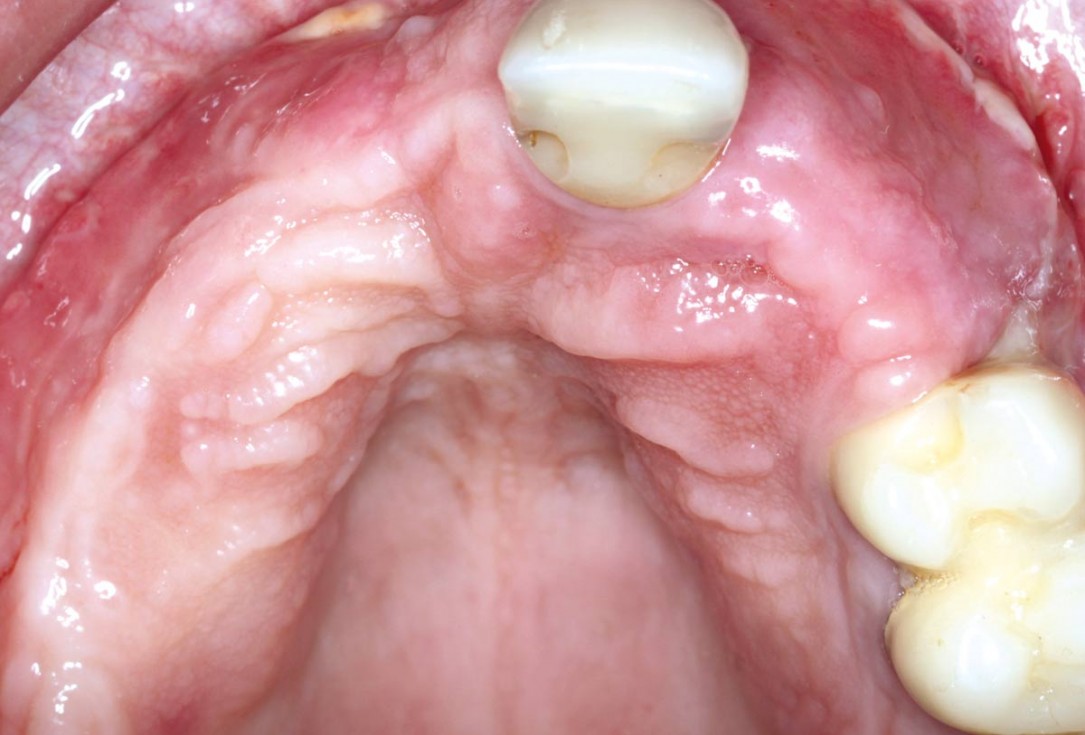

Clinical situation: 71-old patient with atrial fibrillation and Warfarin medication